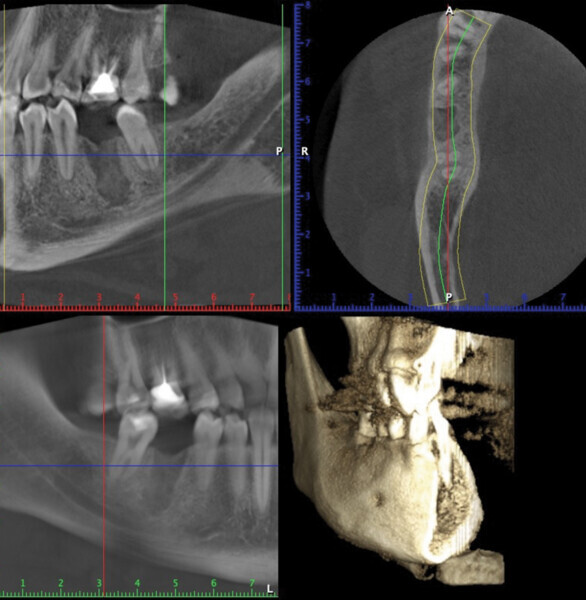

CBCT préimplantaire

Lors de la réouverture pour la pose de l’implant, nous avons pu constater que la hauteur de l’alvéole a été préservée, et la constitution de néo os alvéolaire de belle consistance nous a permis la pose de l’implant en toute sécurité (Figs. 9 et 10).

Fig. 9